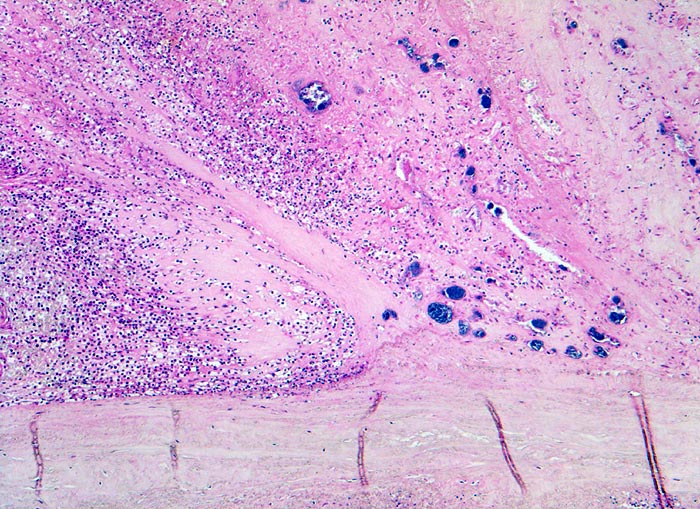

Histologisch findet sich bei ulzeropolypöser Endokarditis ein Fibrin-Thrombozytenthrombus, welcher von Bakterien durchsetzt ist (=Vegetation). Die Vegetation sitzt auf einem Klappendefekt an dessen Basis Granulationsgewebe einzusprossen beginnt, welches den Thrombus organisiert. Klappendefekte, Gefässeinsprossungen, verdickte Sehnenfäden (> 2848) oder Kommissurenverwachsungen (> 8389) der Taschenklappen weisen morphologisch auf eine abgeheilte Endokarditis hin.

• Längsschnitt durch Aorta, Aortenklappe und linkes Ventrikelmyokard.

• Dem ulzerierten Klappengerüst aufgelagerte polypöse Vegetation aus Fibrin und Granulozyten durchsetzt von blauen Kokkenbakterienkolonien (polyposa).

• Ausgedehnte frische Koagulationsnekrose (unsichtbare Zellkerne, Infiltrate neutrophiler Granulozyten) des linken Ventrikelmyokards unterhalb der Klappe.

• Mehrere septikopyämische Streuherde (blaue Bakterienhaufen in intramyokardialen Blutgefässen umgeben von Mikroabszessen).